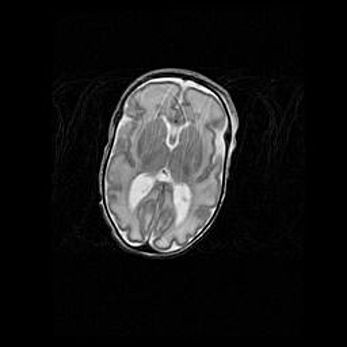

Множественные кисты обоих полушарий головного мозга, наибольшая из них в правой затылочной области. Ассиметричная атрофическая гидроцефалия.

Возраст: 7 месяцев

Вес: 5660 г

Пол: мужской

Окружность головы: 41,5 см

Срок гестации: 28-29 недель

Кисты головного мозга развиваются в результате многоочаговых некрозов вещества мозга и возникают вследствие перенесенной перинатальной инфекции, менингитов, энцефалитов, асфиксии, родовой травмы, расстройств мозгового кровообращения различного генеза. Образованию кист в веществе головного мозга плодов и новорожденных способствуют такие факторы, как высокое содержание в нем воды, недостаточная (или отсутствие) миелинизация и слабая астроглиальная реакция на повреждение.

Кисты могут сочетаться с гидроцефалией и другими поражениями головного мозга.